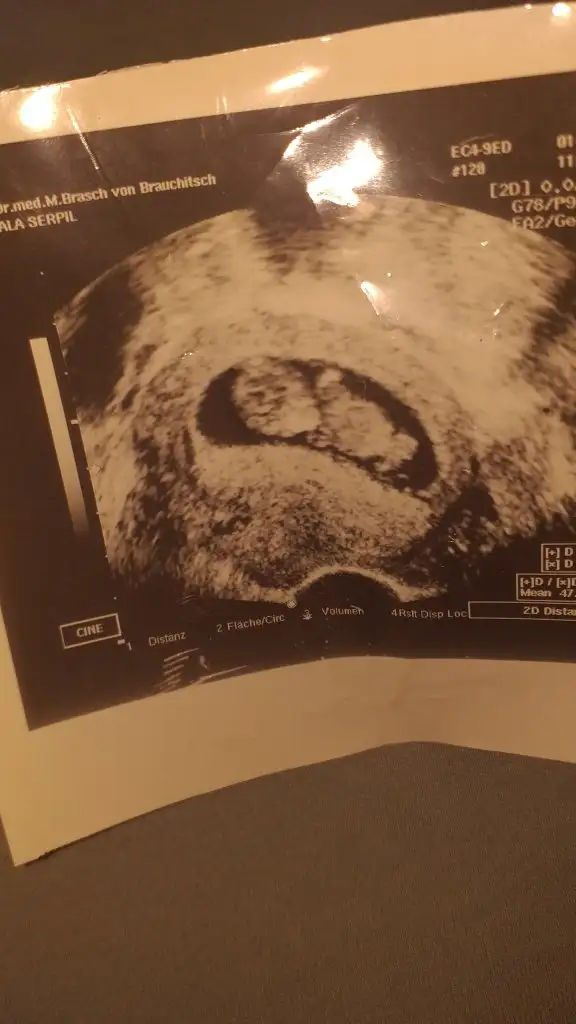

Kız buna göre sen 11 12 13 hafta usg paylaşEki Görüntüle 2656844

Biliyorum belki çok erken ama merak işte 9 haftadayım herhangi bir tahmin yapabilir misiniz

Evet sırt dönük başka yokmu tipi kız sanki ama tutmayabilir nuba bakmadım